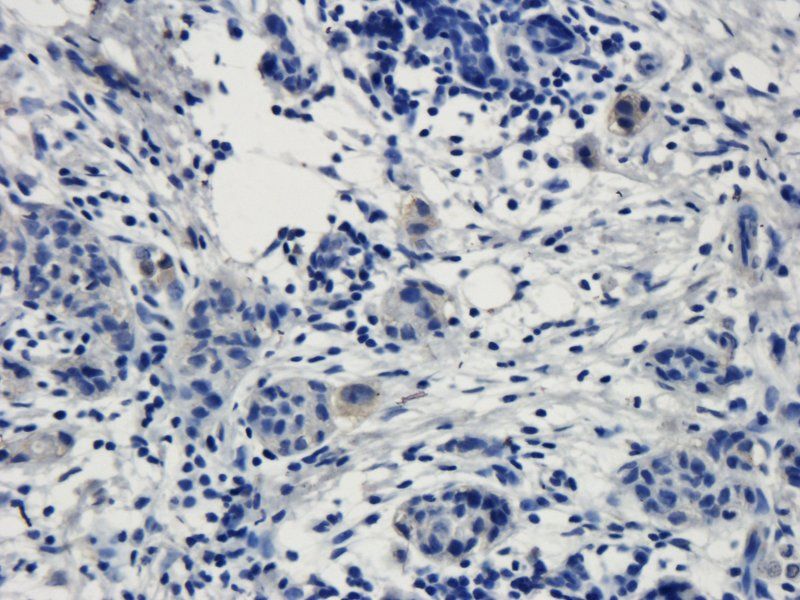

Immunohistochemical staining of human colon cancer using TRPV1 antibody